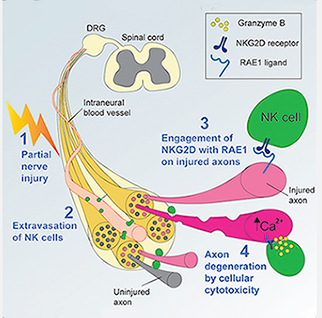

"Imagine a landowner who has trees with unhealthy or dying branches," Davies said. "To generate fresh growth in these trees he or she cuts back the tree to a healthy stump, a process known as coppicing. These trees then have the ability to regrow their branches, similar to our peripheral nerves. You could imagine that NK cells have this partnership with nerves and that when a nerve is damaged it signals to NK cells to essentially come and chop these branches off so they can grow back healthily again."